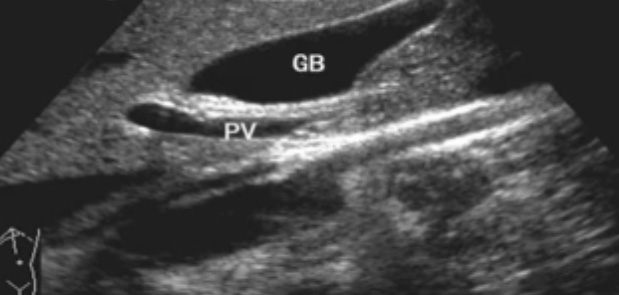

一、正常膽囊超聲圖像有的時(shí)候經(jīng)常發(fā)現(xiàn)檢查不到膽囊,其實(shí)有幾種可能性,檢查人員的技術(shù)不過關(guān)沒發(fā)現(xiàn)膽囊,就要找上級醫(yī)生會診,如果還是沒找到的話就不是技術(shù)問題。結(jié)石或腫瘤充滿膽囊,使其液腔消失,慢性膽囊炎使得膽囊萎縮或膽囊壁肥厚而囊腔消失患者已進(jìn)食,膽囊處于膽汁排空的狀態(tài),膽囊先天性過小或缺失;膽囊位置極端異常(可能很低或位于左側(cè))膽囊切除術(shù)后(注意詢問病史)。